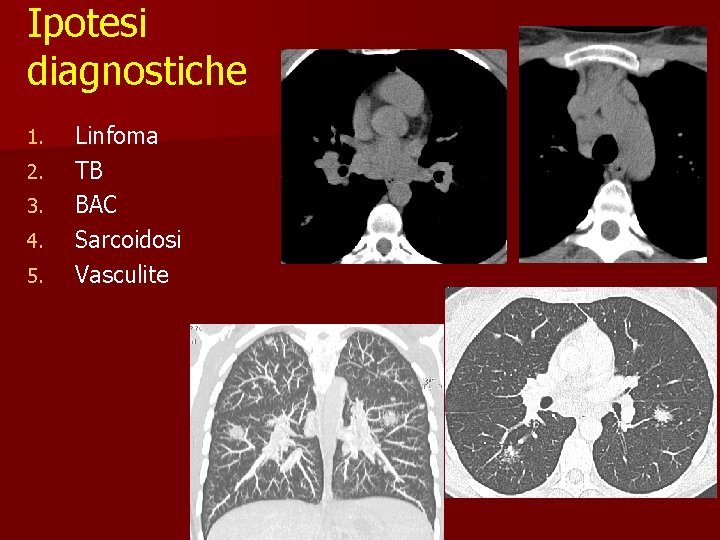

Caso clinico n n n 29 anni Donna Lieve ipertermia Artralgie Non fumatrice Non sintomi respiratori

Ipotesi diagnostiche 1. 2. 3. 4. 5. Linfoma TB BAC Sarcoidosi Vasculite